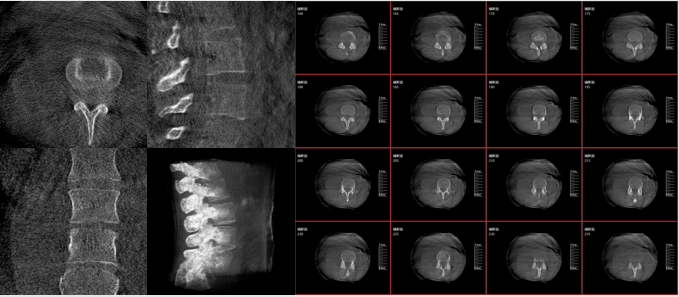

移動(dòng)式三維C形臂影像

術(shù)中三維影像

而三維影像的MPR圖像組可以通過(guò)不同平面的切分,使成像區(qū)內(nèi)更豐富的信息得以呈現(xiàn)。尤其是二維影像無(wú)法涉及的橫斷面,提供了另一個(gè)空間維度的信息量。

作為使用者,醫(yī)生在手術(shù)中雖然有術(shù)前的影像作為判定依據(jù),但每一臺(tái)手術(shù)都具有獨(dú)特性,需要術(shù)中三維影像提供的實(shí)時(shí)信息,作為術(shù)中診療操作的基礎(chǔ)。

在MPR圖像中,冠狀面、矢狀面和橫斷面的信息大大提高了醫(yī)生對(duì)于病灶區(qū)以及手術(shù)效果的判定。